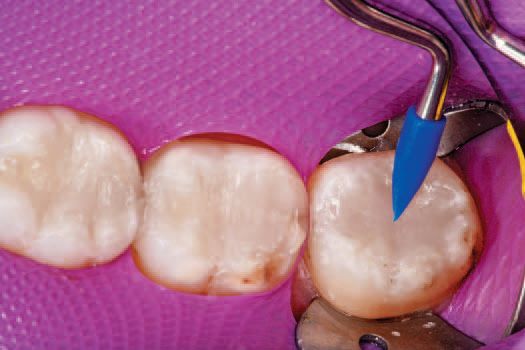

All remaining sharp edges of the preparation were then beveled with Sybron Dental’s Axis fine finishing diamond #846-016, completing the preparations (Fig. 5). Ivoclar Vivadent’s AdheSE® One F self-etch dental adhesive was applied to tooth No. 30 using the VivaPen™ delivery system (Fig. 6), leaving a shiny bonded surface (Fig. 7).

A stream of oil-free, moisture-free air expelled from a warm air tooth dryer from A-dec was then directed over the adhesives to evaporate the solvent (Fig. 8). The adhesive was light cured with Ivoclar Vivadent’s LED curing light, Bluephase Style, for 10 seconds.